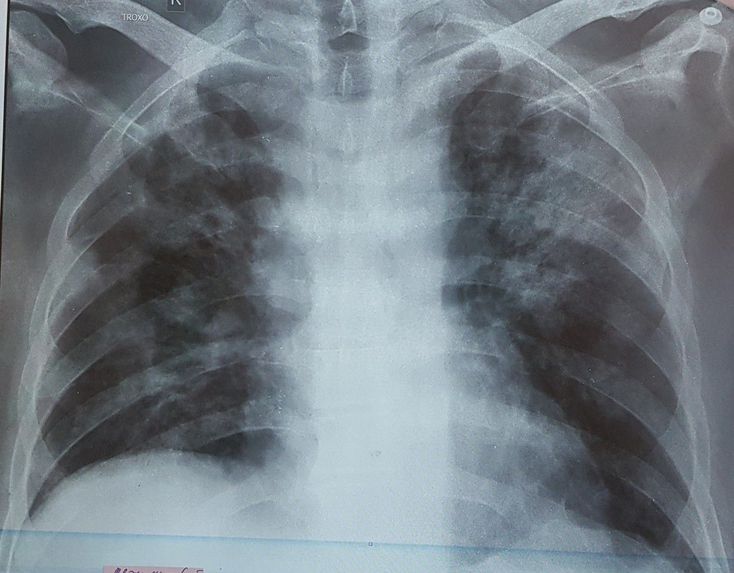

Bizde tedavi lopinavir/ritonavir+arbidol+ gerekirse antibotik kullanimi. Biz bu protokolle suan icin cok iyi durumdayiz. 24 ölum oldu. Ve ilk vaka turkiyedeki ilk vakadan daha once basladi. Covid tanisi Turkiyede koyulurken Cerrahpasadaydim. 1ay suresince calistim. Insallah cabuk sekilde toparlaniriz.